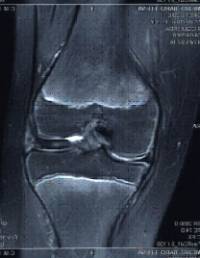

Inestabilitat femoropatelar

És una entitat clínica en què es troba alterat en normal funcionament d’aquesta articulació ocasionat per la descompensació de les estructures retenidores (òssies i / o de parts toves).

La simptomatologia clínica és molt variada i es pot manifestar en forma de dolor rotular, subluxació i luxació de ròtula, esporàdica o inveterada i fractures osteocondrals associades a episodis de luxació.

S’han de valorar detingudament els estabilitzadors ossis i musculolligamentosos que participen en el funcionament d’aquesta articulació a l’hora de plantejar-se el tractament d’aquesta patologia.

El tractament fisioterapèutic i mitjançant ortesis forma part important de l’arsenal terapèutic.

Hi ha diferents intervencions descrites en funció de si cal fer una realineació de l’aparell extensor a nivell proximal, distal o tots dos i en funció de la presència del cartílag de creixement fèrtil.

En els pacients en edat pediàtrica és molt freqüent l’associació d’aquesta entitat a la presència d’una ròtula alta (determinada per l’índex d’Insall) per la qual cosa fem servir la tècnica descrita per Galleazzi mitjançant tenòdesi amb tendó semitendinós autòleg i secció artroscòpica de l’aleró rotulià extern.